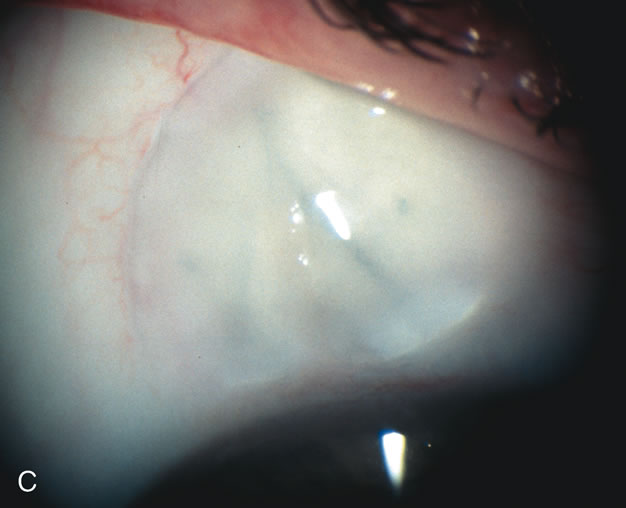

Fig. 3. Partial bleb failure following clear corneal phacoemulsification with foldable IOL. A. Preoperative bleb appearance prior to temporal lens extraction. Preoperative IOP was 12 mm Hg on no antiglaucoma medications. Time from 5-FU trabeculectomy surgery to lens extraction was one year. B. Bleb appearance 2 months after clear corneal cataract surgery with topical anesthesia. Following lens extraction, increased vascularity was noted along with decreased size of the filtering bleb. IOP increased to 20 mm Hg as early as 2 weeks after surgery, necessitating topical antiglaucoma therapy. C. High magnification view of bleb before lens extraction demonstrates diffuse pale bleb. D. High magnification view of bleb 2 months after surgery. There are vessels surrounding the nasal side of the bleb and the overall bleb size is smaller.